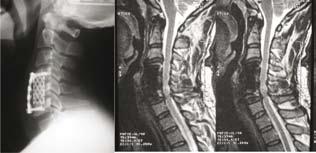

■此病人的頸椎椎管狹窄,頸的脊髓神經受壓。X光片及磁力共振顯示之前的醫生只幫他做了一個前路融合,並沒有進行神經減壓,因此他的情況變得更糟糕,需要進行翻修手術。

■利用電腦導航技術幫病人進行翻修手術,再做後路神經減壓,並且精確地利用椎弓根螺絲去固定他的頸椎,紓緩他的痛楚。